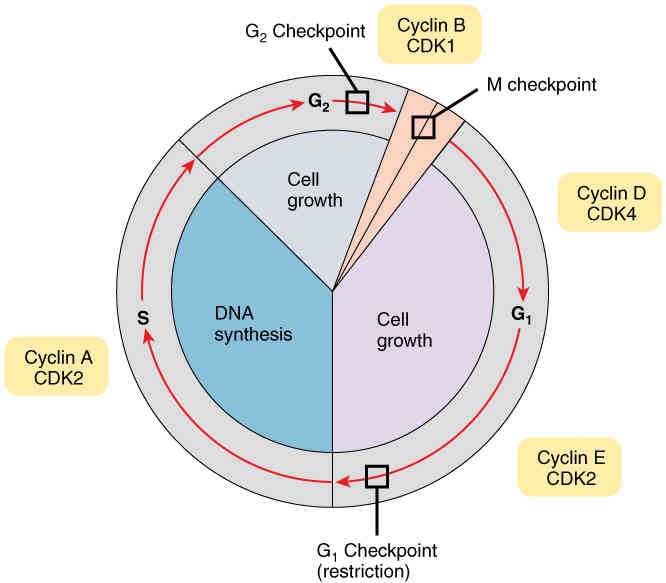

This page is under construction. For now, it is just a resource of the images found in the OpenStax Anatomy and Physiology Handbook. It wil slowly change into a revision tool. Each slide has a number. Use this to refer to the slide. When completed, it will have an unlabelled section, with labelled slides in parallel. On the unlabelled slides, write your answer and use the labelled slide to assess yourself. Keep track by also noting the number on each slide. Improvement at each attempt is important, more so than full marks on a first attempt.